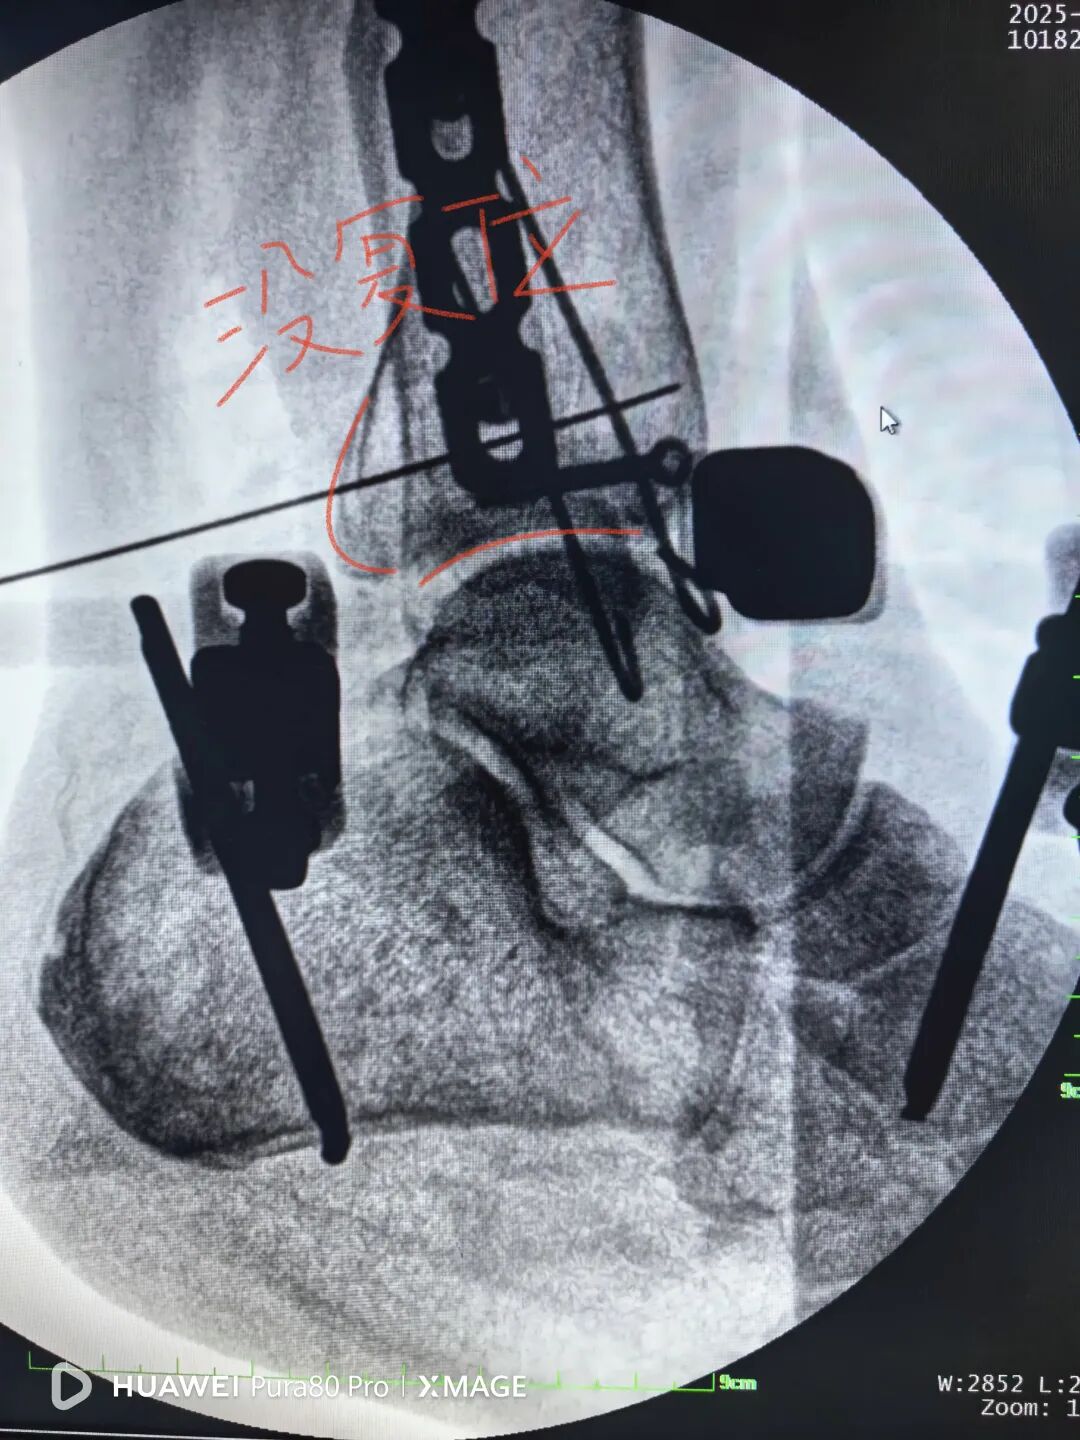

术后复查:

下胫腓关节复位良好

但前侧Chaput骨块

后侧volkmann骨块都移位